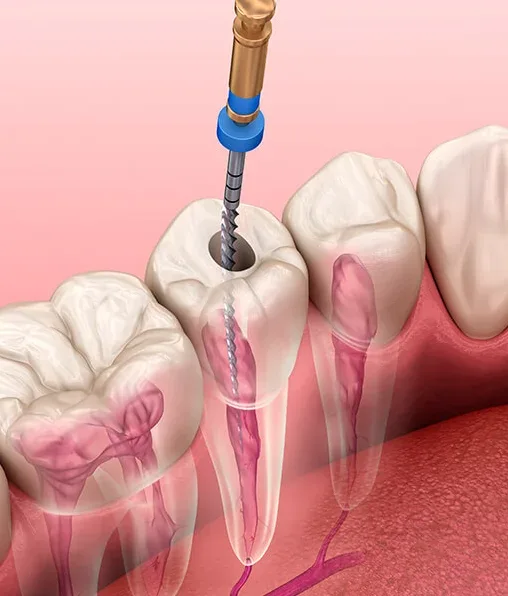

O tratamento remove a polpa infectada e desinfeta os canais radiculares.

Durante o tratamento, você pode esperar um procedimento tranquilo e seguro.

O dentista irá anestesiar a área afetada para assegurar seu conforto.

Após a limpeza e desinfecção, o dente será obturado para proteção.